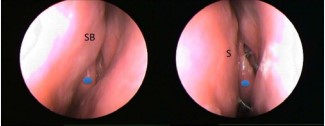

At the 3 month follow-up, the average pre-op NOSE score of 41.6 was reduced to 17 at 3 month follow-up (p<.05), and the average pre-op NSB endoscopy score of 2.5 was reduced to 1.0. Figure 2

Figure 2: Endoscopic view of right nasal cavity before and after NSB RFA. Note white dot on anterior tip of middle turbinate S = septum, IT = inferior turbinate, SB = swell body, arrows = RFA site

shows a pre-op and post treatment endoscopic image of a right sided NSB, and Figure 3

Figure 3: Endoscopic view of left nasal cavity showing NSB before and 6 months after RFA. Blue dot on anterior tip of middle turbinate. SB = swell body, S = septum

shows the same patients 6 months after the RFA procedure. Note the obvious improvement in endoscopic visualization of the ipsilateral middle turbinate. After 6 months, the average NOSE score 20.6 (p<.05), and the average NSB endoscopy score was 1.2.